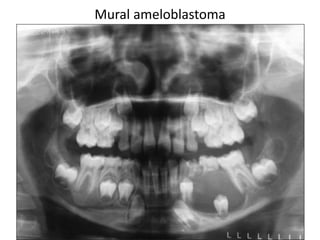

Mural ameloblastoma

Mural (Unicystic) Ameloblastoma